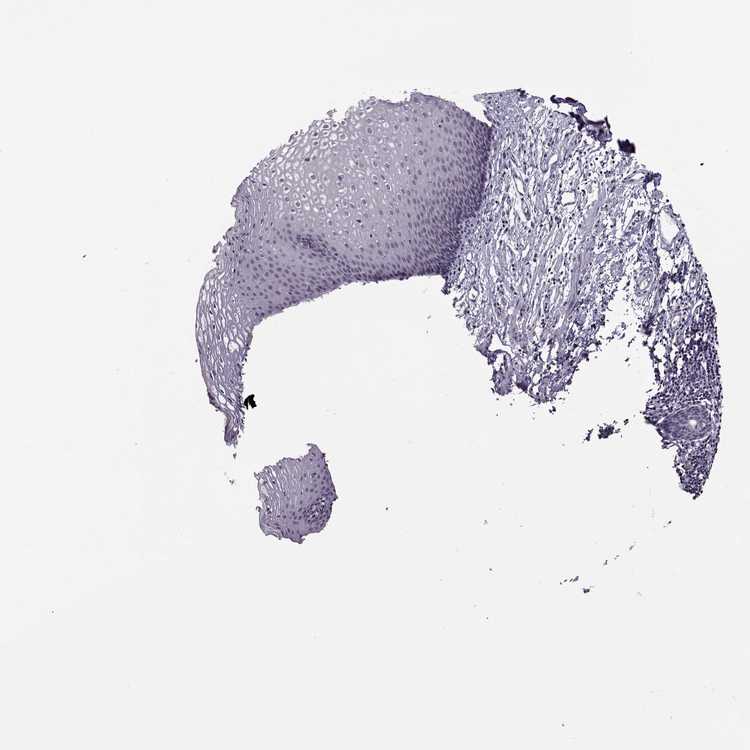

ESOPHAGUS - Antibody stainingi

Antibody staining in the annotated cell types in the current human tissue is reported as not detected, low, medium, or high, based on conventional immunohistochemistry profiling in selected tissues. This score is based on the combination of the staining intensity and fraction of stained cells.

Each image is clickable and will lead to virtual microscopy that enables deeper exploration of all samples and also displays staining intensity scores, fraction scores and subcellular localization as well as patient and tissue information for each sample.

Antibody HPA037992

Squamous epithelial cells Not detected